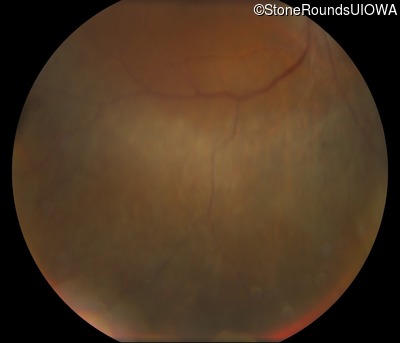

Fundus Photography - Right - 20/50 -3

Fundus Photography - Left - Count Fingers 6"